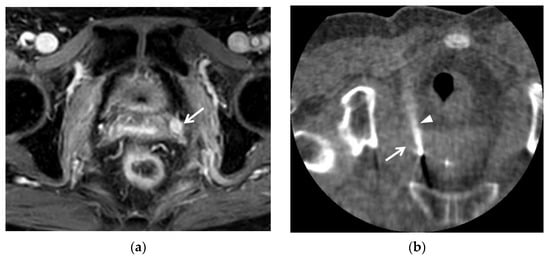

3.2. T1WI Findings

8. Lymph Node Metastasis